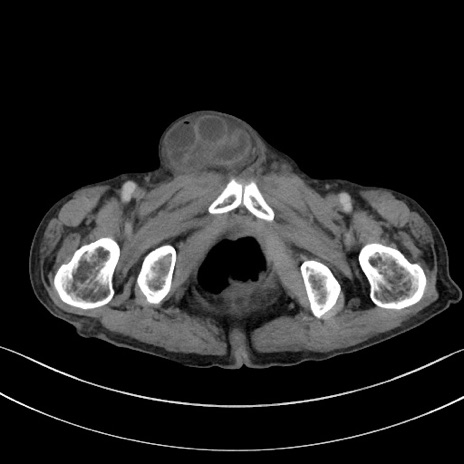

症例3(横断像)

【症例】 70歳代男性

【主訴】右鼠径部腫瘤、疼痛

【現病歴】本日朝より上記主訴あり、受診。

【既往歴】膀胱癌にて膀胱全摘、両側尿管皮膚瘻

【データ】WBC 5600、CRP 0.56